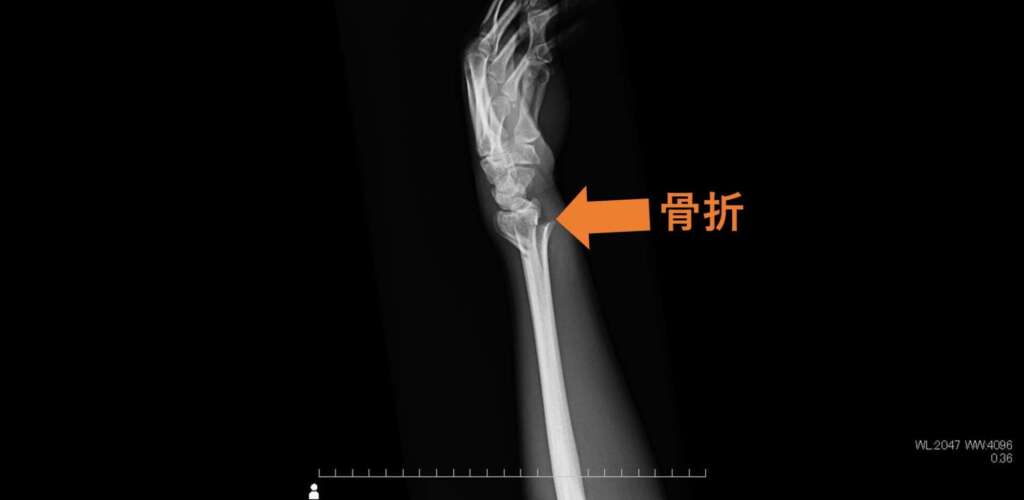

全身の骨の撮影では、骨折や関節の変化を明瞭に観察することができます。